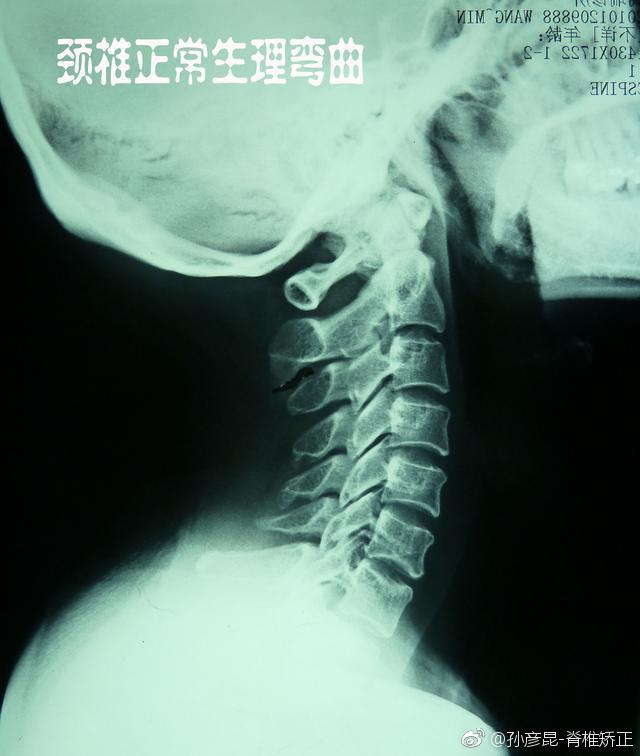

生理曲度对颈椎的影响

正常颈椎生理曲度:完美的曲线,没有退行性病变,椎间盘良好,没有骨刺,看着很舒服。